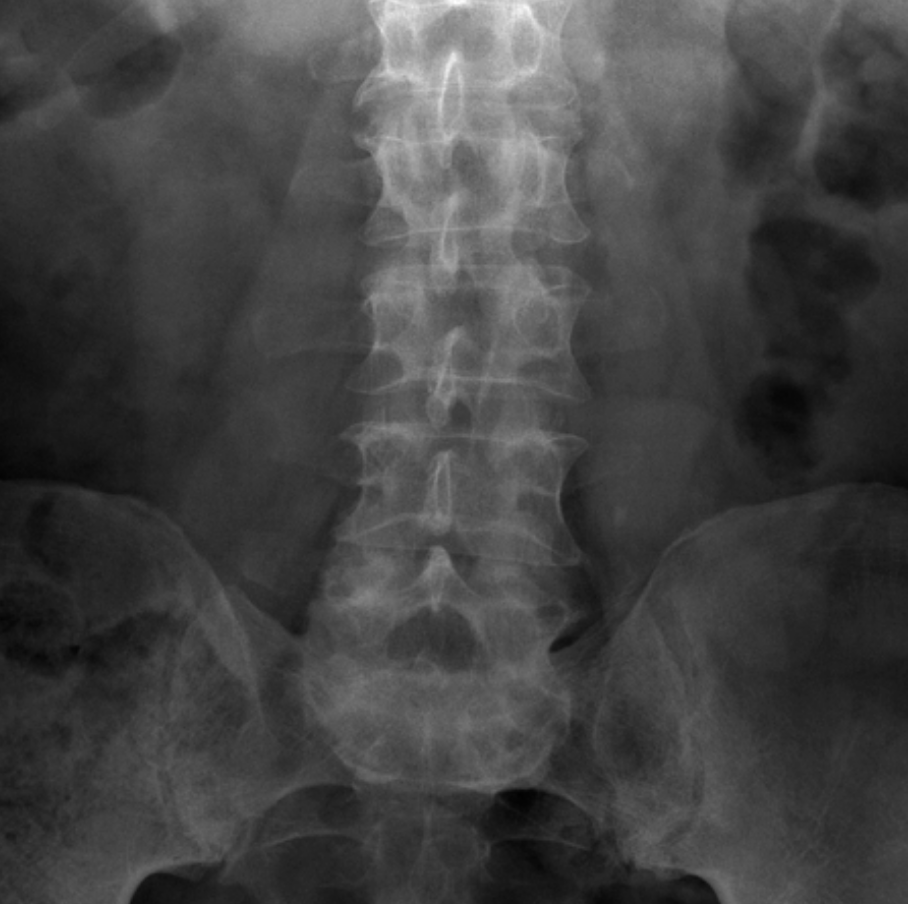

Take a look at the following example showing consolidation. Click on the box to reveal the diagnosis.

Diagnosis

Neck of femur fracture